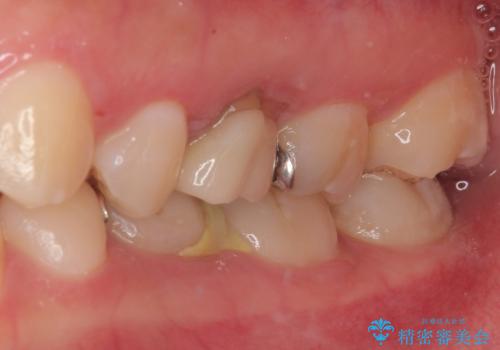

治療後特に問題もなく見た目、噛み合わせともに満足していただけました。

今後はメンテナンスで通ってもらいながら経過を観察する予定です。

レントゲン上で金属の詰め物(メタルインレー)の下に虫歯を認めた為、オールセラミッククラウンでの治療と、乳歯なので予後を考えインプラントによる補綴治療もご提案しましたが、患者様の強い希望によりオールセラミッククラウンでの治療となりました。